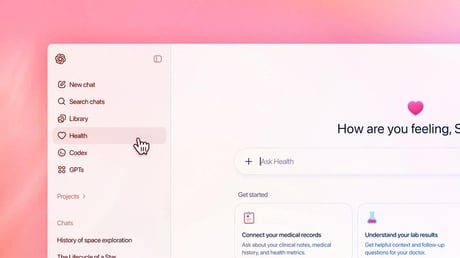

Az OpenAI nem használja fel egészségügyi adataidat MI-képzéshez

Az OpenAI elindítja a ChatGPT Health nevű új funkciót, amely kizárólag egészségügyi beszélgetésekre készült, és biztonságos, privát teret kínál a felhasználóknak. A funkció...

A mesterséges intelligencia már az orvosnál is segít: itt a ChatGPT Health

Az OpenAI egy új egészségügyi funkcióval bővíti MI-csevegőjét, amely segít eligazodni az orvosi viziteken és a saját egészségügyi adataid között. A ChatGPT Health...